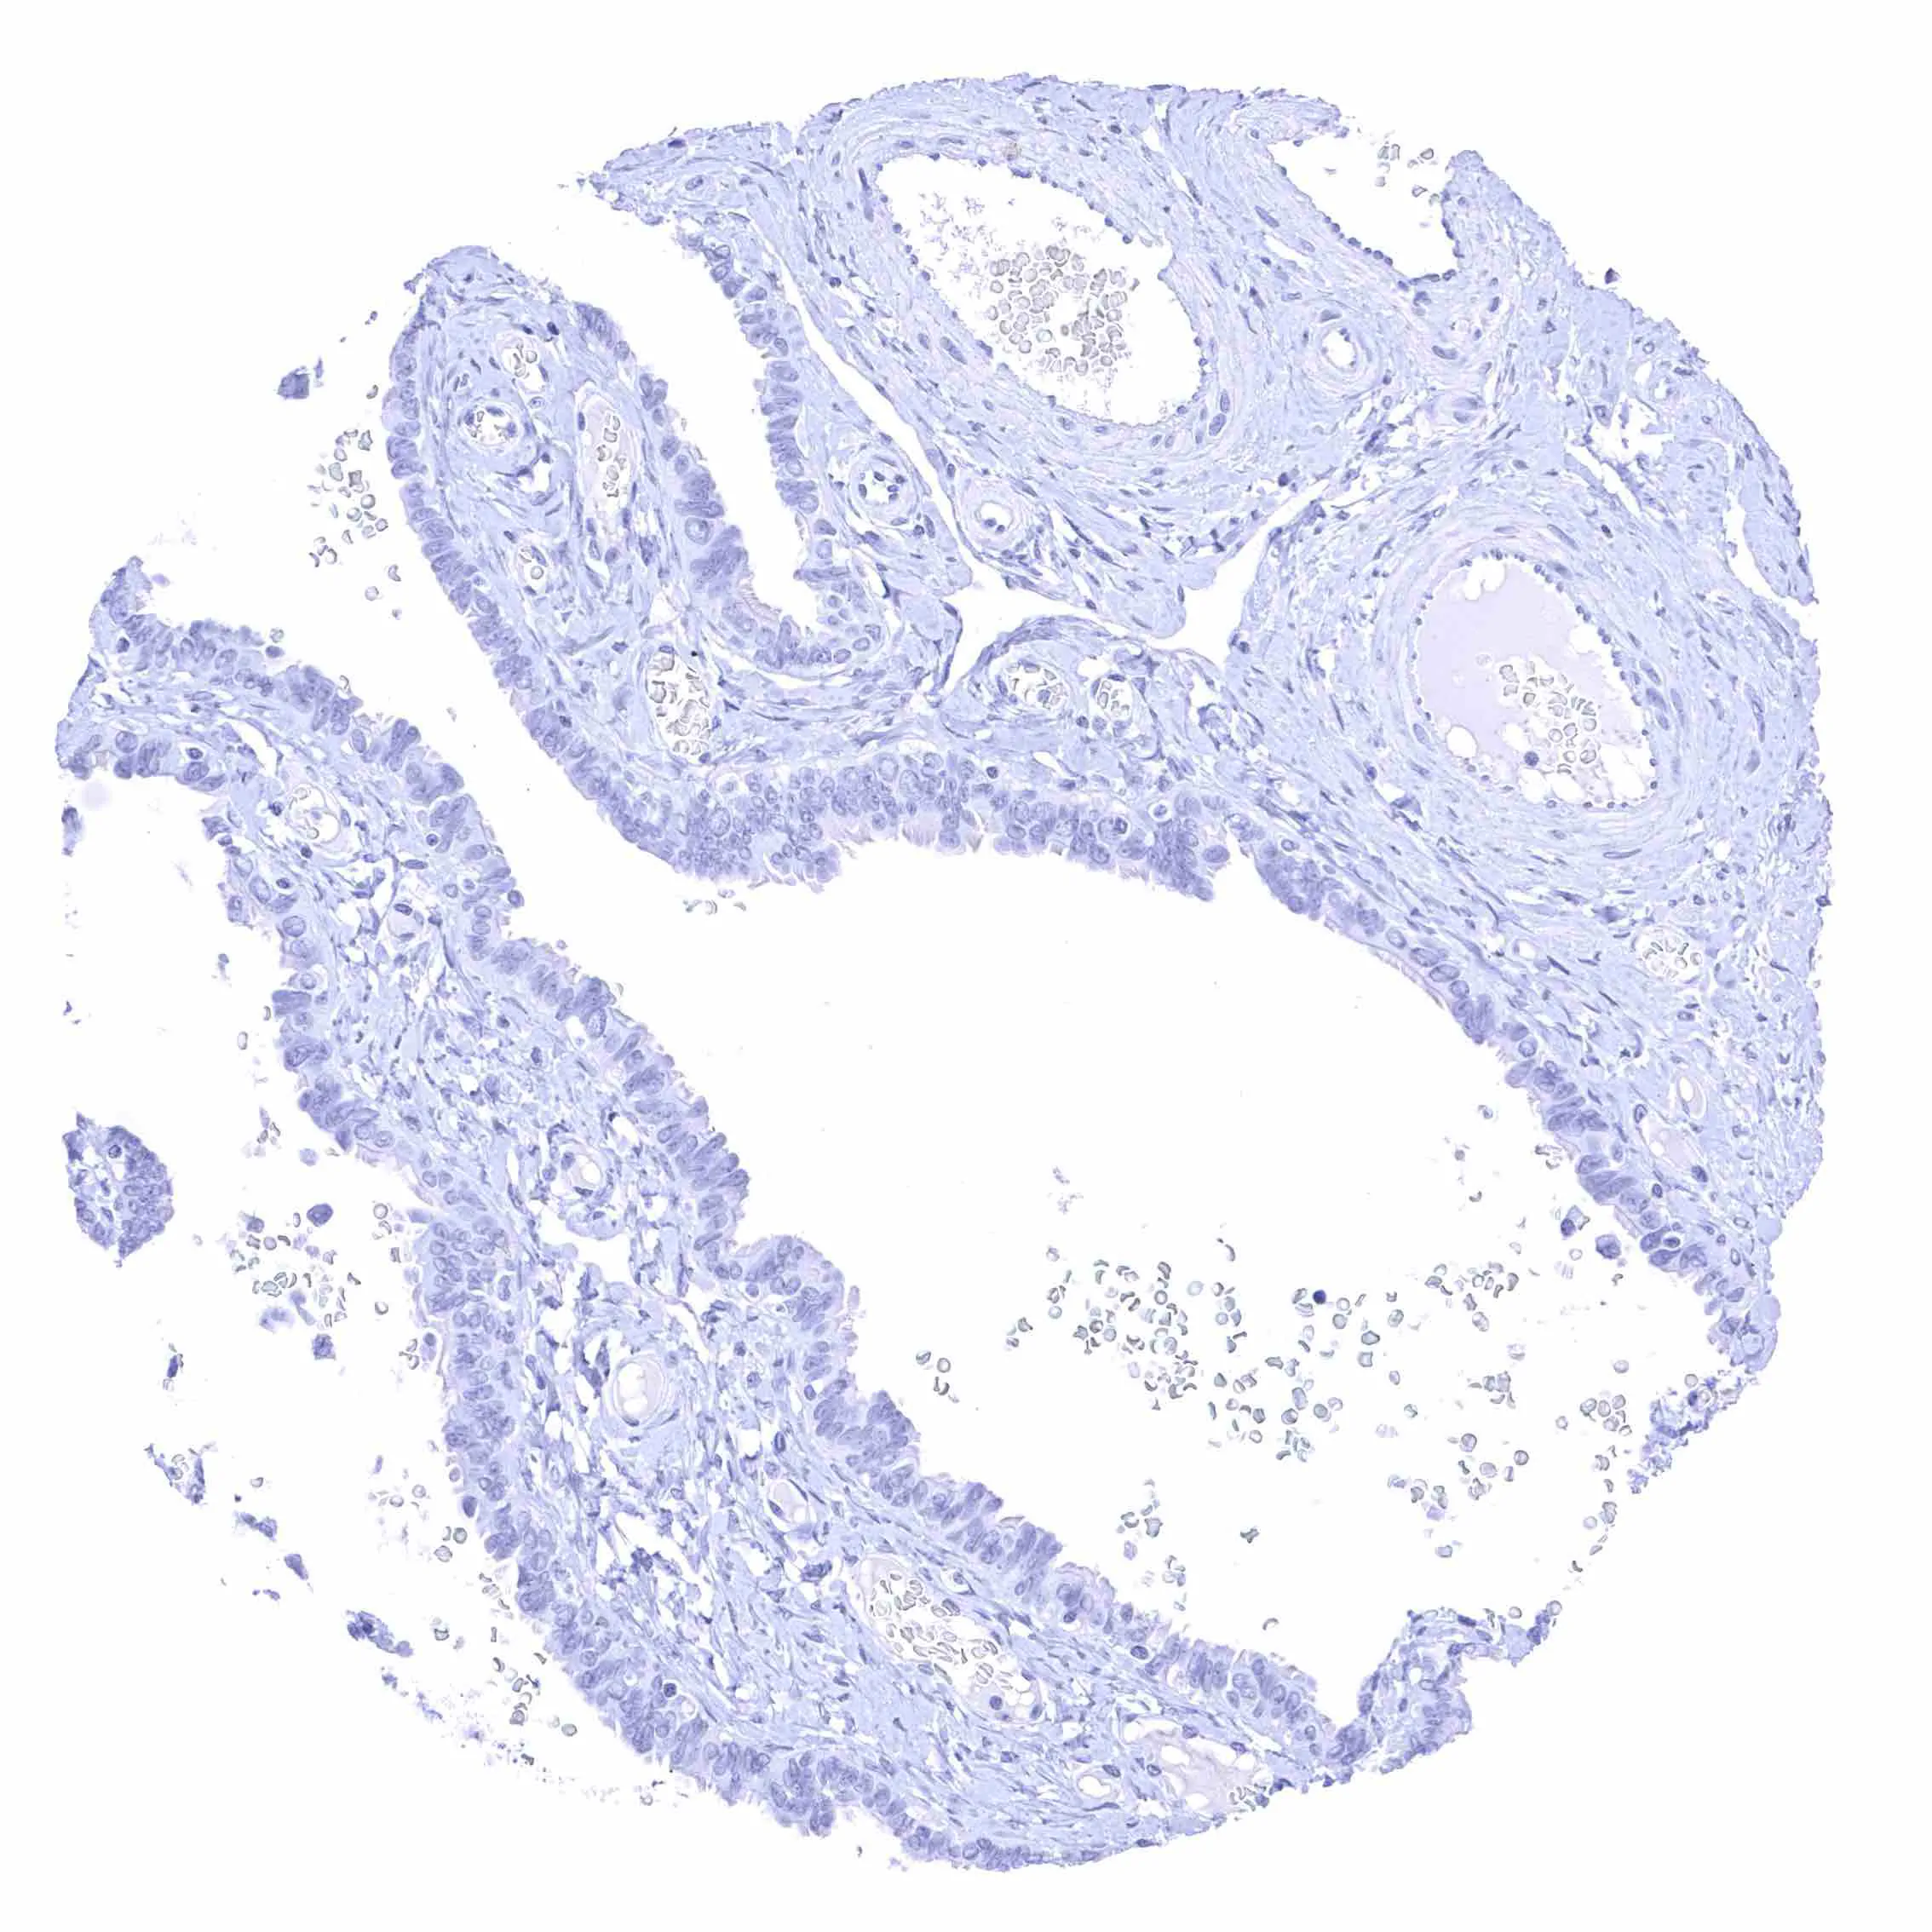

Fallopian tube, mucosa